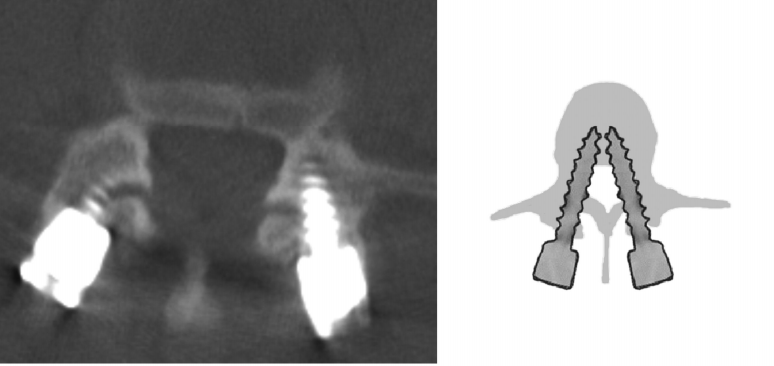

对于椎弓根螺钉损伤关节突关节的影像学评估,目前已有的临床研究主要依据内固定术后CT扫描观察螺丝、螺帽或连接杆对关节突关节的损伤程度。本期我们将已有的分级系统进行汇总,为大家术后评估和进一步研究提供参考。

2级:螺钉进入关节腔内,但进入距离<1 mm(右)

左侧1级,右侧2级

左侧1级,右侧0级